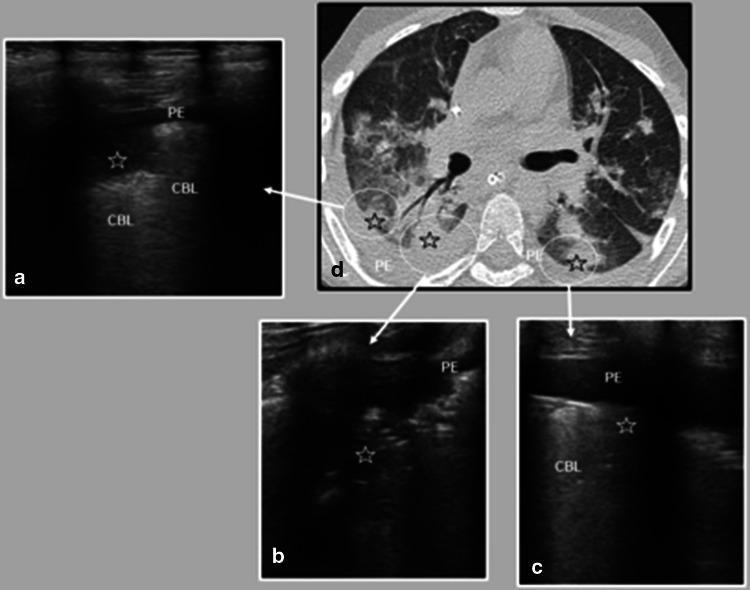

Thirty-four confirmed COVID-19 patients had a lung US performed during this period. Eighteen (18/34) had abnormalities on the lung US, but eight of them (8/18) had a normal chest radiograph. Ultrasound lung aeration score medians for severe/critical, moderate, and mild disease were 17.5 (2-30), 4 (range 0-14), 0 (range 0-15), respectively (p = 0.001). Twelve patients (12/34) also had a chest computed tomography (CT) performed; both the findings and topography of lung compromise on the CT were consistent with the information obtained by lung US.

在此期间,34例确诊的COVID-19患者接受了肺超声检查。18例(18/34)肺超声检查有异常,但其中8例(8/18)胸部X线片正常。重症/危重症、中度和轻度疾病的超声肺通气评分中位数分别为17.5(2 - 30)、4(范围0 - 14)、0(范围0 - 15)(p = 0.001)。12例患者(12/34)还进行了胸部计算机断层扫描(CT);CT上肺损伤的表现和部位与肺超声检查获得的信息一致。